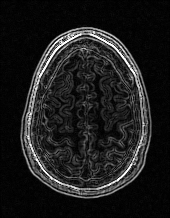

Edge preserving has always been a crucial concern in the design of reconstruction models. To improve the quality of reconstructed images and preserve image edges, some works suggested introducing edge priors in the original restoration problem to preserve image edges [4, 34]. However, they will suffer from complicated algorithm design and time-consuming training processes. Recently, some more efficient methods have been proposed to use edge maps as external guidance for image restoration. For example, Yang et al. [48] used off-the-shelf edge detectors to extract image edges from the degraded images. Fang et al. [12] predicted image edges by constructing an edge reconstruction network. Huang et al. [18] designed a novel dual discriminator GAN framework for solving fast multi-channel MRI, in which one GAN network is built for edge information enhancement. Inspired by these methods, we also consider introducing image edge prior as external guidance to MRI reconstruction since 1) image edges are prominent and distinguishable features in MRI (see Fig. 1), which can serve as a good guide to the model to recover high-frequency details; 2) the ground truth edges can be easily fetched via ordinary edge extraction operators, like Canny, Sobel, and Prewitt, which means that the edge maps can be learned in a data-driven manner. However, how to effectively utilize image edge priors to guide image reconstruction still remains a challenge. In some methods, edge information was simply concatenated with the input image and passed to the next stages. Though this is a simple way to utilize the edge priors, it may not give full play to the guiding role of the edge priors. Therefore, in this work, we want to explore a more efficient and effective mechanism to fully take advantage of image edge priors.

(a)

(b)

(c)

fastMRI is a large-scale MR dataset jointly established by Facebook AI Research and NYU Langone Health. It provides both knee and brain datasets for evaluation. In our work, we use the multi-coil knee dataset, which was acquired on three clinical 3T systems or one clinical 1.5T system using a 15-channel knee coil array. The dataset includes data from two pulse sequences, yielding coronal proton-density weighting with (PDFS) and without (PD) fat suppression. As is shown in Fig. 1, PD images usually contain more structural and prominent edge features than PDFS images, which suggests that it is more challenging to use edge guidance on PDFS datasets. Therefore, we explore the effectiveness of EAMRI on these two modalities. Following [13], for both PD and PDFS knee datasets, we separately filter out 227 volumes (8332 slices) for training and 24 volumes (1665 slices) for testing. The dataset is centrally cropped to .